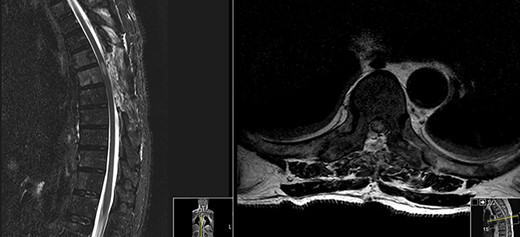

Spinal magnetic resonance imaging (MRI) (Fig. 1) showed an hyperintense contrast-enhancing abnormal mass at the level of T6 which occupied the left side of the spinal canal and compressed the spinal cord.